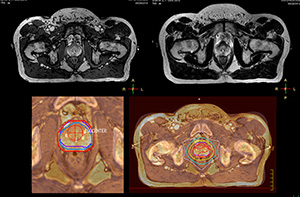

“We currently use MR-RT mainly in the abdomen and pelvis region: prostate, colorectal, pancreatic, cervical, and liver. Also in the brain, we are starting to use it,” says Dr. Yan.

Impressive clinical benefits for prostate

“The biggest problem for CT-based planning, especially in prostate, is you can’t see the cancer very well,” says Dr. Stevens. “On CT it can be quite challenging to see the edge of the prostate especially at the apex. When the edge of the prostate can’t be delineated well on CT, radiation oncologists will increase their margins a little bit so they don’t miss it, but that can also increase toxicity.”

“Using MR, the prostate is well delineated. We quickly see the edges of cancerous tumors like in prostate cancer, and as normal structures can be defined, we can optimize the treatment plan to protect these organs and their normal function. This can potentially improve the outcome. And it improves workflow as well. We can contour more quickly, confident that the tumor is going to be in the field.”